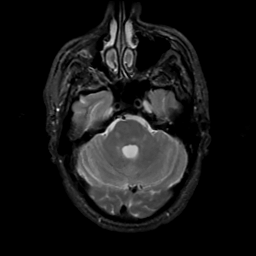

MR Study #6, March 17, 1991 -- Slice #13

[Home][Help][Clinical][Tour 1][Tour 2] Slice 13